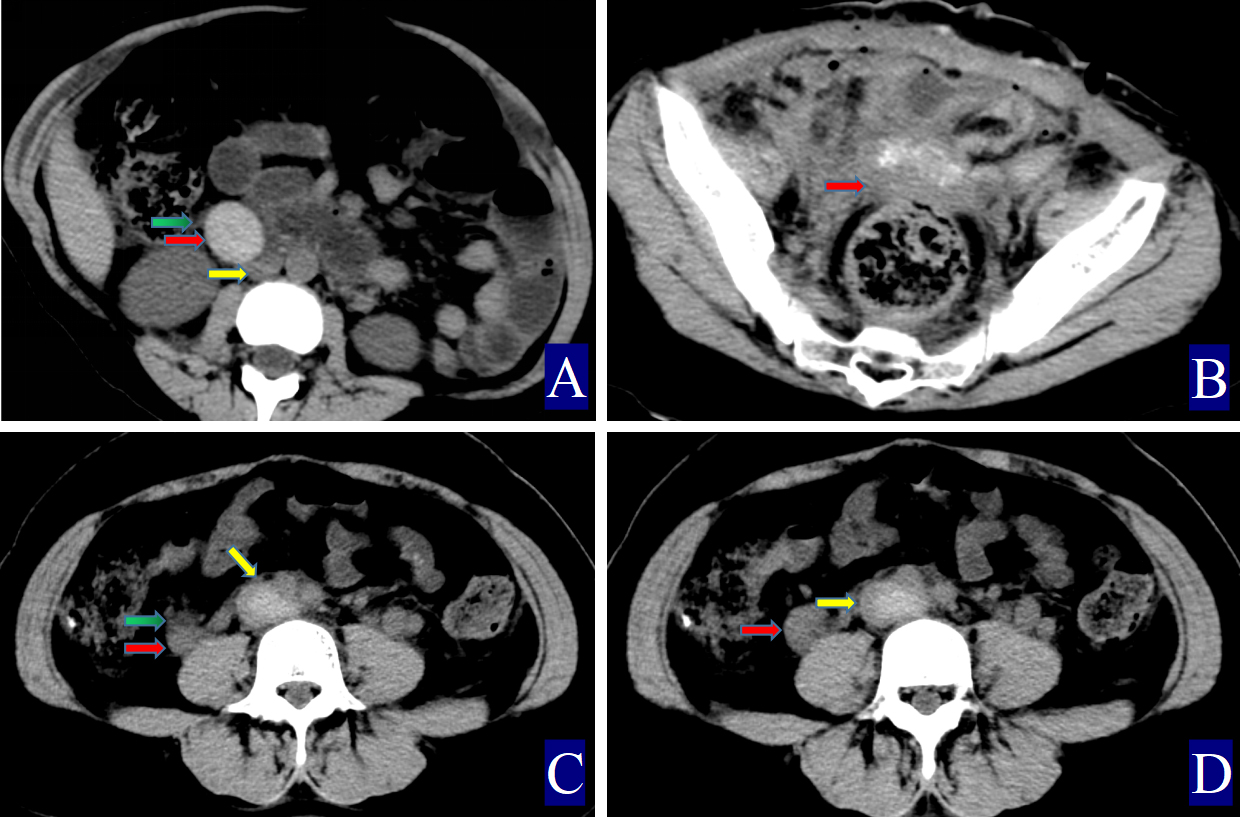

Fig. 1. A 24-year-old woman with right ovarian vein thrombophlebitis. The red arrow indicates the ovarian vein, the yellow arrow indicates the inferior vena cava, and the green arrow indicates the periovarian vein exudate. (A) Non-contrast axial CT image. The right OV is approximately 1.4 cm wide (CT value = 52.00 HU, red arrow). The inferior vena cava shows a CT value of 32.40 HU (yellow arrow), with visible surrounding exudation (green arrow). (B) Contrast-enhanced sagittal CT image. A filling defect is observed in the right ovarian vein, consistent with POVT, and the vessel wall appears uniformly thickened (red arrow). (C) Contrast-enhanced axial CT image. The right ovarian vein shows a clear filling defect, and the vessel wall is uniformly thickened (red arrow). (D) Three-dimensional vein reconstruction. The inferior vena cava is marked (yellow arrow), with the right OV shown as a thin red arrow and the left OV as a thick red arrow.

The primary CT findings of POVT included filling defects within the ovarian vein lumen along with thickening of the vessel wall (Figs. 1,2,3). Secondary signs involved pelvic effusion in 13 cases and periovarian venous exudation with increased fat density in 19 cases (Figs. 1A,C,3A,C). One patient, who developed extensive thrombosis extending to both lower extremity veins, the inferior vena cava, and pulmonary arteries, died from postpartum hemorrhagic shock. The remaining 23 patients fully recovered.

Compared with the non-POVT group, the POVT group showed significantly greater ovarian vein width on the thrombus side, higher CT attenuation of the thrombus-side ovarian vein, as well as increased CT attenuation difference and ratios (p = 0.001, Figs. 1,2,3). Using 0.90 cm as the cut-off value for ovarian vein width, the sensitivity reached approximately 91.70%, with a specificity of 95.20% (Figs. 1A,2A,3A,C,D). With 46.00 HU as the threshold for ovarian vein CT value on the thrombus side, both sensitivity and specificity were 100% (Figs. 1A,2A,3A). For a CT attenuation difference cut-off of 12.50 HU, the sensitivity was 95.30%, and specificity remained 100%. Similarly, a ratio cut-off of 1.1 yielded a sensitivity of 95.30% and specificity of 100% (Figs. 1A,2A,3A).

Direct signs observed on CT included variable widening of the ovarian vein, increased intraluminal density, and filling defects, often accompanied by vessel wall thickening, which is in line with prior reports [16, 17, 18, 19, 20, 21] (Figs. 1,2,3). A notable finding in our study was the identification of previously undescribed indirect signs: increased fat density around the ovarian vein in the pelvis and the presence of small-volume pelvic effusion (Figs. 1A,3A–D). These signs may reflect the local inflammatory reaction associated with thrombophlebitis.

Semi-quantitative parameters from non-contrast CT scans revealed clear differences between the POVT and non-POVT groups. The thrombus-side ovarian vein width, CT attenuation of the thrombotic ovarian vein, the difference between ovarian and inferior vena cava CT values, and their ratio were all significantly higher in the POVT group (p = 0.001, Figs. 1,2,3). These parameters may serve as reliable diagnostic references. For instance, using 0.90 cm as the cut-off for ovarian vein width yielded a sensitivity of approximately 91.70% and a specificity of 95.20%. This supports earlier findings [5] that vein enlargement is a key feature of POVT (Figs. 1,2,3). A CT attenuation cut-off of 46.00 HU for the thrombotic ovarian vein achieved 100% sensitivity and 100% specificity (Figs. 1,2,3). Similarly, a CT attenuation difference threshold of 12.50 HU and a ratio cut-off of 1.1 also demonstrated strong diagnostic performance (Figs. 1,2,3). However, in one patient with extensive thrombosis of the inferior vena cava, the ovarian vein had a lower CT value than the cava, resulting in a negative difference (–12.50 HU) and a ratio of 0.83, reflecting variability in advanced or complex cases. Currently available non-invasive diagnostic tools for POVT include Doppler ultrasound (sensitivity 52%), magnetic resonance imaging (MRI) (92%), and contrast-enhanced multidetector CT (100%) [5]. The present study indicates that non-contrast CT semi-quantitative parameters can closely match the diagnostic accuracy of enhanced CT, while offering greater simplicity, lower cost, and avoiding the risks associated with contrast agent use.